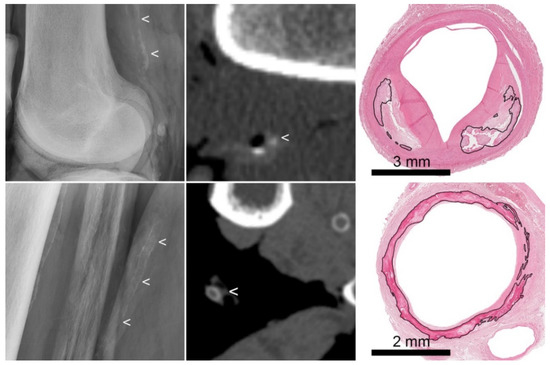

3.2. Radiography

3.3. Computed Tomography